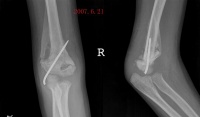

1.常有肘关节损伤史,多见于青少年。

2.早期以肘关节活动时疼痛为主,肘关节活动受限。

3.在肘关节周围可以摸到异常骨块,该骨块可逐渐增大,以后又可缓慢回缩至骨块成熟。

骨化好发与肱前肌,表现为肘关节区肿胀与疼痛,肘关节被动与主动活动均受限。疼痛与肿胀减退后在肘关节前方可以摸到一个界线清楚的硬的肿块。因肌肉无弹性,故肘关节伸屈受限;由于肿块的阻挡,屈曲也明显受限。

x线特征:受伤后不久可出现局限性肿快。伤后3-4周,在肿快内显示毛状致密象,其临近骨将显示骨膜反应。伤后6-8周,病变边缘部清楚地被致密骨质所包绕,而具有新生骨的外貌。软组织肿块的核心部有时显囊性变且逐渐扩大其内腔,到晚期而显出类似蛋壳状的囊肿。伤后5-6个月肿块收缩,因而肿块与邻近的骨皮质和骨膜反应之间显出x线透亮带。